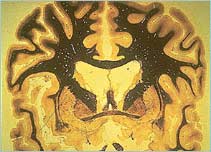

Section through the brain

Coronal section through a human brain showing the thalamus and caudate nucleus. Courtesy of University of Wisconsin, Dept. of Anatomy